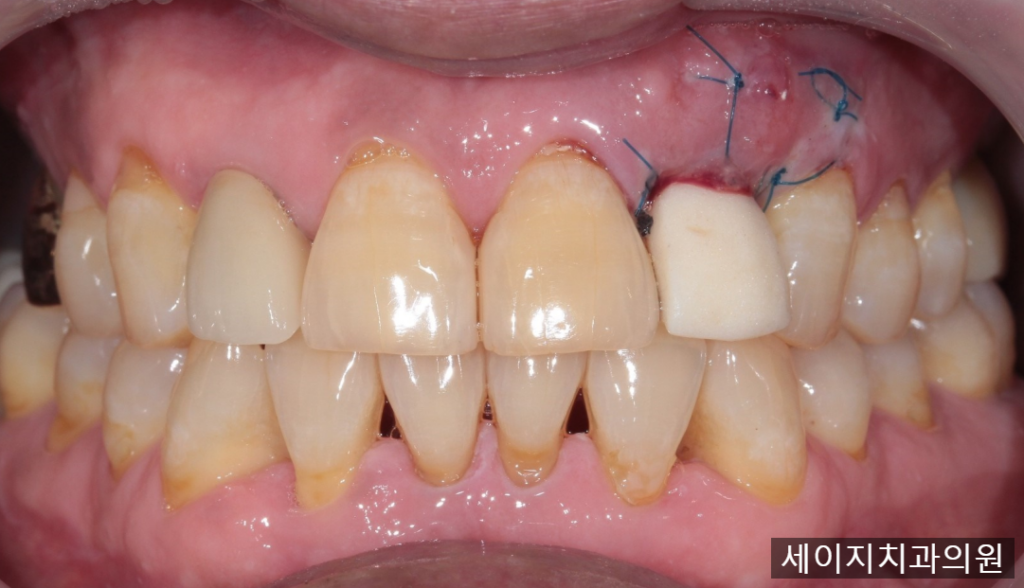

올바른 위치에 임플란트를 식립하고 나서, 채취된 잇몸편을 원래 계획하였던 위치에 봉합하였습니다.

수술 후 즉시 임시치아를 제작하여 간섭되지 않도록 조정해 드렸으며 잇몸이 치유될 수 있도록 수회의 소독을 시행해 드렸습니다. 이후 일정 기간의 임플란트와 뼈의 융합기간을 기다려 임플란트 보철물을 제작해 드렸습니다.

보철물의 장착 직후 증대된 잇몸이 보철물에 눌려 하얗게 바뀐 모습이 관찰됩니다. 치아의 발치 이후 소실되었던 잇몸뼈로 인해 얇아진 잇몸에 임플란트의 금속 구조물이 비쳐보이지 않을까하여 충분한 결체조직이식술을 시행했고, 결과적으로는 잇몸이 증대되어 심미적인 요소 또한 충족시킬 수 있었습니다.